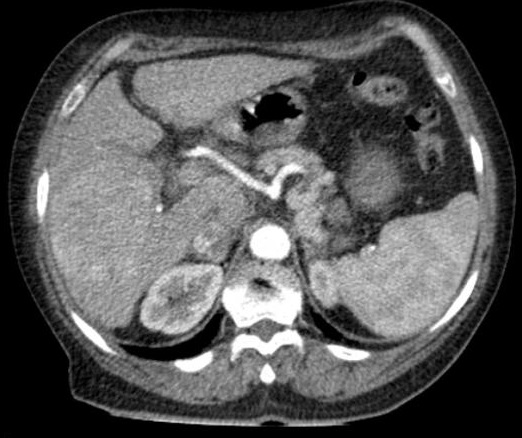

Image TDM en coupe axiale

avec injection de contrast hydrosoluble

intraveineuse , phase ảrteriel : Aspect lesionaire

hyperdense en forme nodulaire d'une HCC du foie

droit . Foie en cirrhotique a petit volume , bord

irregulier |